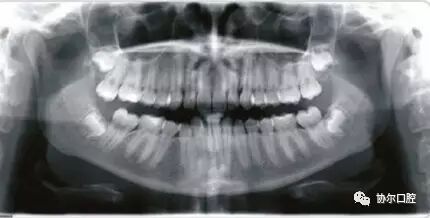

i-PAN功能,利用一项独一无二的专利使KaVo 3D eXam i成为一个功能上二合一的系统,不仅可以获取3D影像,而且可以获取常规2D全景图像。

CRANEX D 可进行标准成人全景摄影,小儿全景摄影,区域全景摄影,TMJ摄影,鼻副窦摄影和头颅定位摄影。将前牙扫描层厚增加50%,提高前牙区图像质量,并使病人定位简便。

所有全景摄影程序均采用自动颈椎补偿,减少前牙区重叠伪影,使前牙区结构显示更加清晰